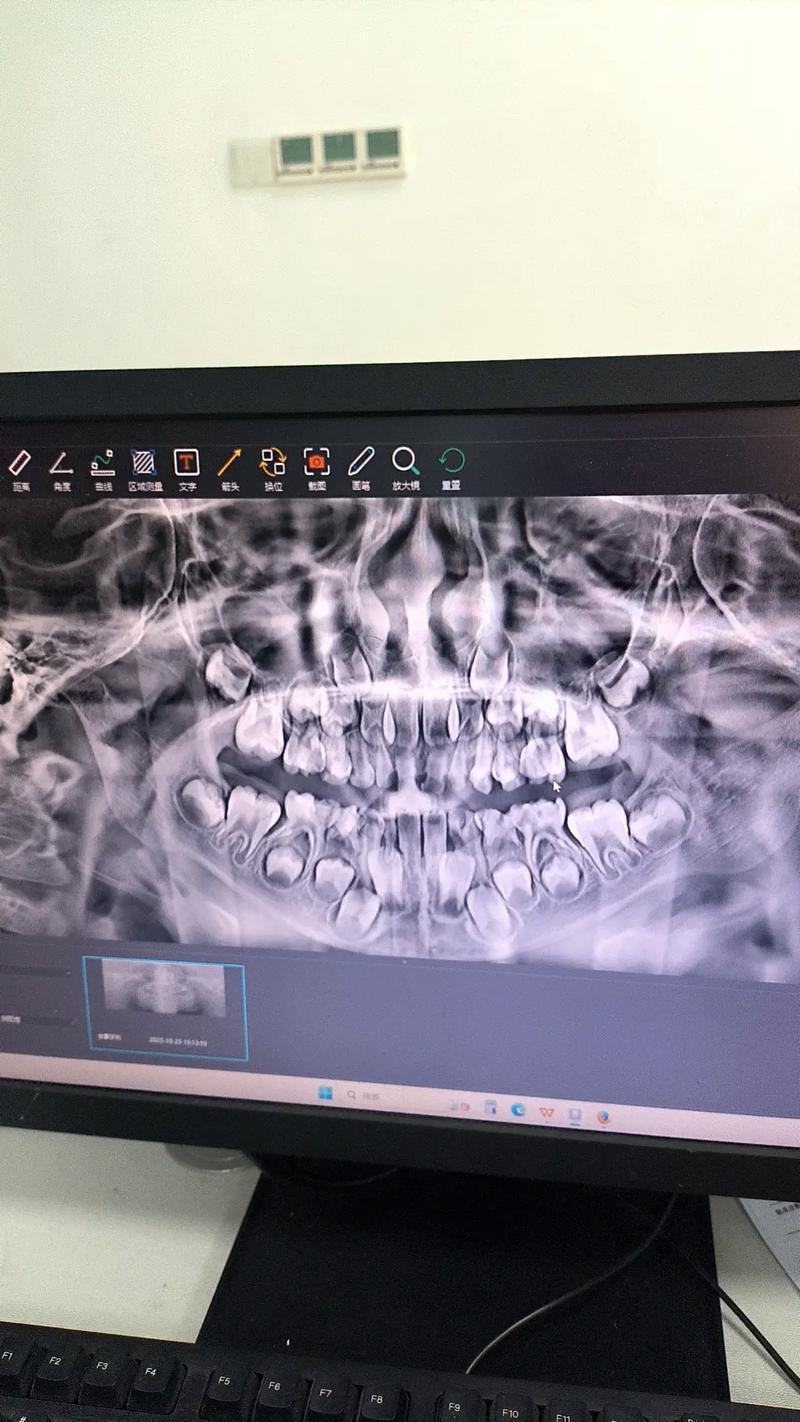

种植牙作为目前公认的理想缺牙修复方式,其成功与否离不开精准的术前规划,而锥形束CT(CBCT)正是种植牙术前评估的核心工具,与传统二维X光片相比,CBCT能通过三维成像技术,清晰呈现颌骨的立体结构,为医生提供关键的解剖信息,从而降低手术风险,提高种植体长期稳定性。

CBCT是一种专为颌面部设计的低剂量三维影像设备,其原理是通过锥形X线束围绕患者头部旋转扫描,经计算机处理后重建出高分辨率的三维图像,与传统CT相比,CBCT具有显著优势:辐射剂量极低(约为传统CT的1/10至1/100),扫描时间短(通常10-30秒即可完成),且成像精度高达0.1mm,能清晰显示牙槽骨的厚度、高度、密度,以及重要的神经血管走向,为种植方案设计提供精准依据。

在种植牙术前评估中,CBCT的作用不可替代,它能精准测量缺牙区骨量,种植体需要植入足够的骨组织内才能获得初期稳定性,CBCT可三维重建颌骨模型,精确测量骨宽度、高度、骨皮质厚度,判断是否需要植骨、骨增量或选择短种植体,上颌后牙区常因上颌窦气化导致骨量不足,CBCT能清晰显示上颌窦底位置及黏膜厚度,指导医生安全进行上颌窦提升术;下颌后牙区则需避开下牙槽神经管,CBCT可精确标注神经管位置与牙槽嵴的关系,避免术中损伤。

CBCT能评估骨密度,影响种植体选择,骨密度与种植体初期稳定性密切相关,CBCT通过灰度值分析可初步判断骨密度类型(如D1-D4类骨),帮助医生选择合适的种植体表面处理方式(如喷砂酸蚀、钛喷砂等)及直径长度,在低密度骨中,医生可能选择更长直径的种植体或进行初期稳定性增强处理。